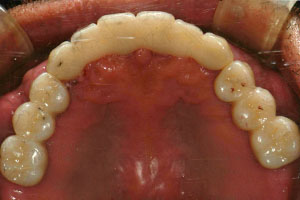

치료증례 전후사진

Before & After